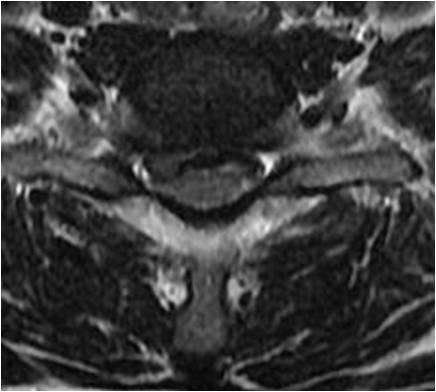

第一天,我跟随张教授上手术。其中一位患者是颈椎后纵韧带骨化症,压迫颈髓局限,张教授进行颈后路2节段椎板切除术。还有一位是脊髓型颈椎病,未充分减压,仅行单节段固定融合术。次日查房,这两位患者的症状得到迅速的缓解,表现出较好的满意度。通过这2例病例,张教授认为:颈后纵韧带骨化症患者,其产生脊髓压迫的主要责任部位在C4、C5,只需针对行减压手术即可;脊髓型颈椎病患者,其产生的病理因素主要是存在颈椎不稳,只要稳定脊柱,就可控制症状。强调对产生症状的病理因素进行有效减压这种理念贯穿于张教授治疗疾患的始终。

颈椎病产生的病理因素是椎间盘,无论是神经根型、还是脊髓型颈椎病。因椎间盘退变可导致脊髓、神经根等受压,亦可形成后方骨赘。那么处理该问题时,就不应该切除椎体,而应该以针对性椎间隙减压即可。所以,张教授在行颈前路手术时,均以单间隙减压充分为目的。无一例行椎体次全切手术。他强调:如有可能,尽量进行单节段固定、融合,强调零切迹的Zero-P的使用。这样,稳定程度高。